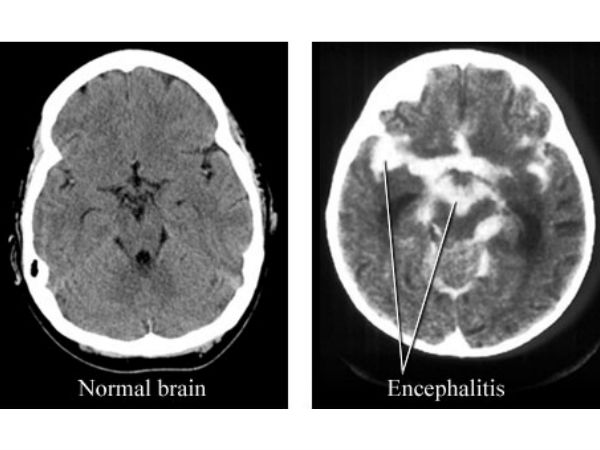

மூளை வீக்க நோய் பாதிப்பு குறித்து கண்டறியும் கருவிகள் கூட அங்குள்ள மருத்துவமனைகளில் இல்லாததால் பெரும்பாலானோர் இறக்க நேரிட்டுள்ளது.

உத்தரபிரதேச மாநிலத்தில் கடந்த 2009ம் ஆண்டு இந்த வகை மூளை வீக்க நோயால் 2,612 பேர் பாதிக்கப்பட்டு பல்வேறு மருத்துவமனைகளில் அவர்களில் 441 பேர் உயிரிழந்தனர் என்பது நினைவிருக்கலாம். இந்த கொடுமையான வியாதி ஏழை மக்களை தான் வெகுவாக தாக்குகிறது. இந்நோய்க்கு இதுவரை எவ்வித மருந்தும் கண்டுபிடிக்கப்படவில்லை என்பது குறிப்பிடத்தக்கது.